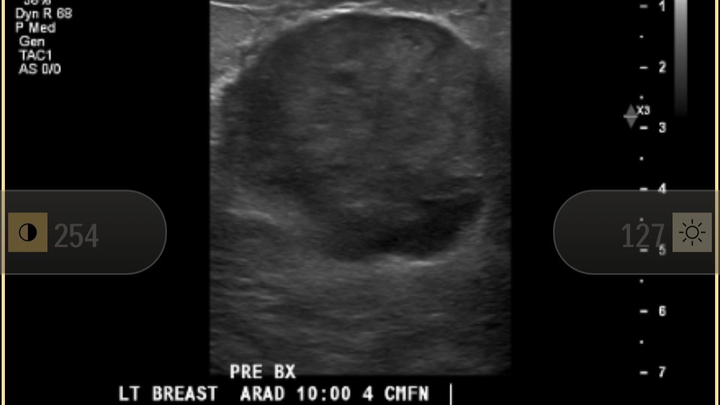

In November, I went in for a routine OBGYN appointment. Nothing exciting. No drama. I had what I thought was a cyst in my left breast. Had one before - no big deal.

Cut to January: diagnostic mammogram, ultrasound, biopsy the following week.

On January 27, I was diagnosed with metaplastic triple negative breast cancer — a rare and aggressive form of breast cancer that’s sneaky and likes to spread to distant organs via the bloodstream.